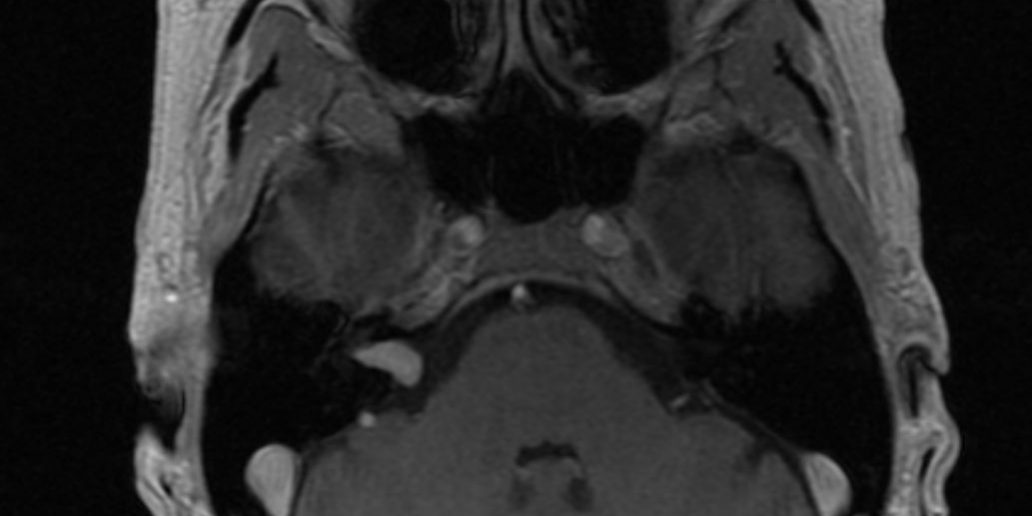

Ασθενής γυναίκα, 53 ετών με εμβοές. Σχεδόν φυσιολογική ακοή δεξιά.

Η μαγνητική τομογραφία εγκεφάλου ανέδειξε μικρή εξεργασία στον δεξιό έσω ακουστικό πόρο, συμβατή με ακουστικό νευρίνωμα (αιθουσαίο σβάννωμα).